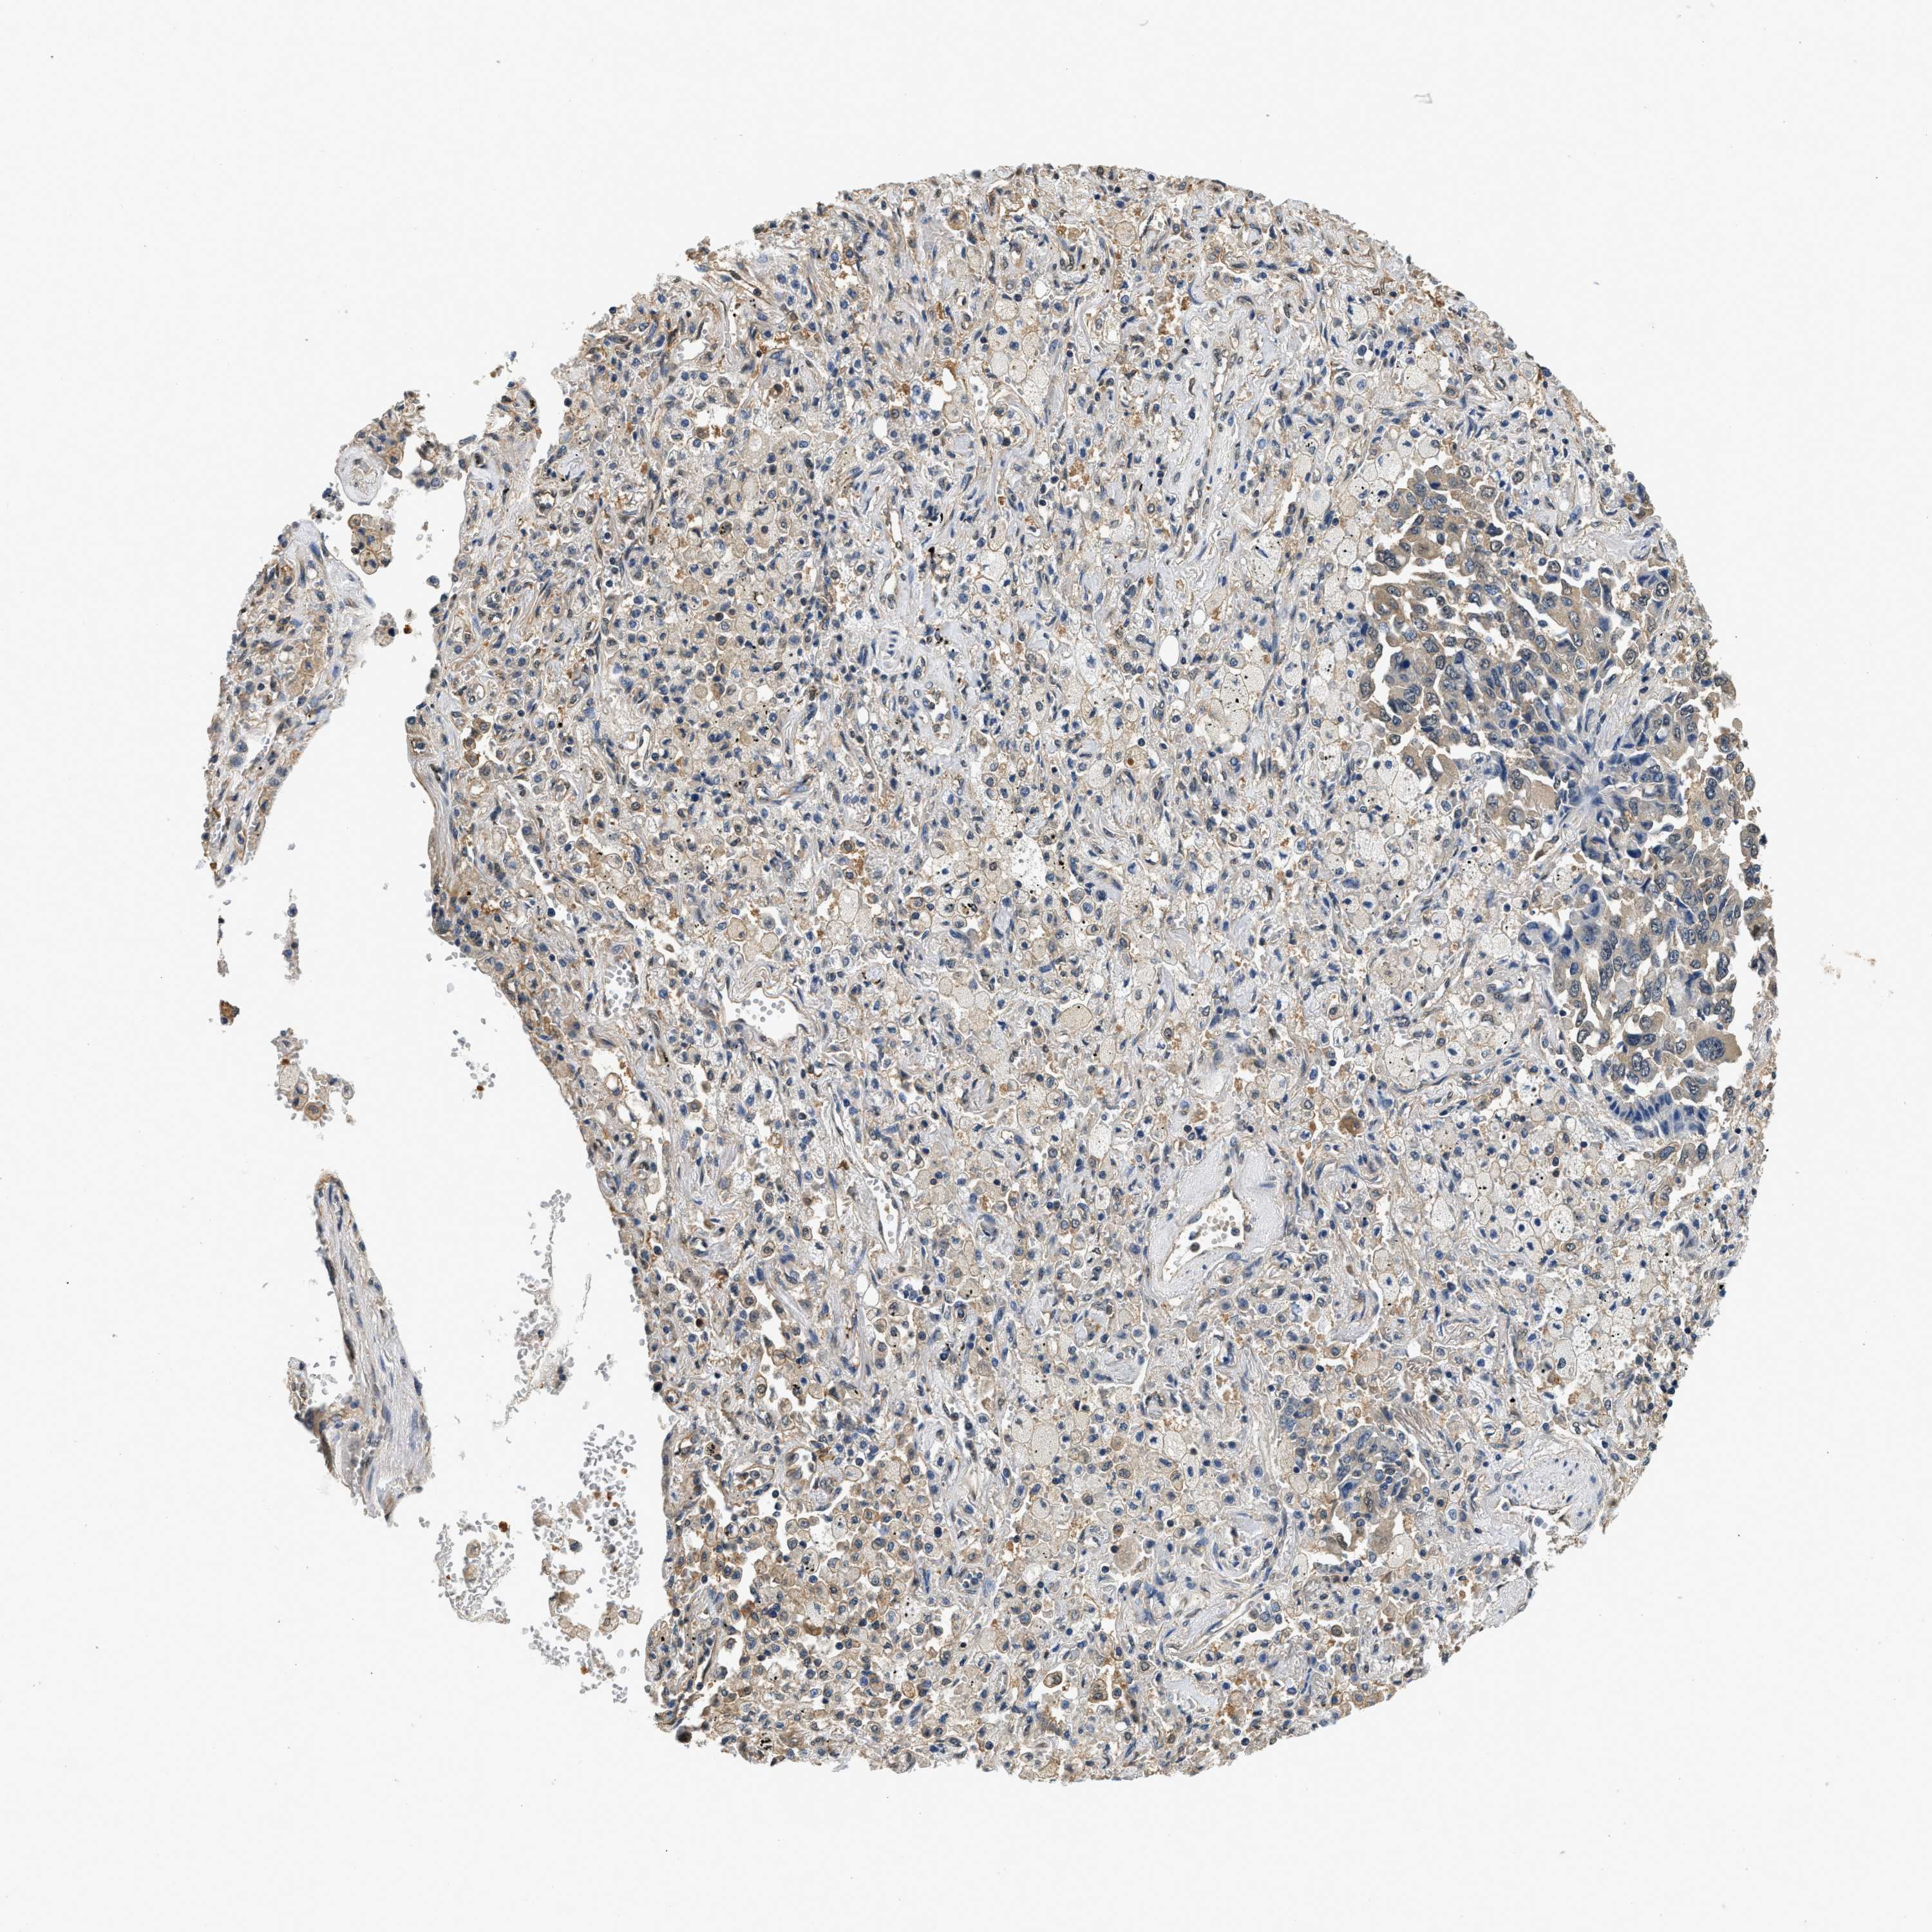

BCL7C

• BCL7C

CANCER LUNG CANCER Show tissue menu

Lung cancer

Human cancer

Lung adenocarcinoma

Lung squamous cell carcinoma